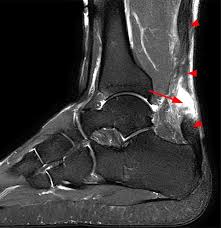

Haglund Deformity Radiology : Haglund Deformity Radiology Case Radiopaedia Org - Haglund's deformity is named after patrick haglund, who defined the condition in 1927.. This condition is often precipitated by wearing shoes with rigid backs that rub against the heel. Does haglund's deformity go away? Haglund deformity, also known as a pump bump , bauer bump, or mulholland deformity, is defined as bony enlargement formed at the posterosuperior aspect of the calcaneum. Haglund's deformity is characterized as an enlarged prominence of the superior aspect of the posterior calcaneus, which can cause painful inflammation within the retrocalcaneal bursa and anterior surface of the achilles tendon as a result of mechanical irritation. Insertional achilles tendinopathy retrocalcaneal bursitis haglund deformity (i.e.

The authors describe a new method of radiologic measurement of haglund's deformity, based on a radiologic study of 31 feet operated for posterior heel pain and more especially for calcaneal tendinopathies related to deformity of the calcaneus, and on a series of 60 asymptomatic feet. As associated problems such as heel bursitis settle, the size of the lump should reduce, but the bony why is it called haglunds deformity? Radiographic evaluation of haglund's deformity. Haglund deformity is most common in young women who wear high heeled shoes or pumps. This deformity leads to retrocalcaneal bursitis. Haglund's deformity is named after patrick haglund, who defined the condition in 1927. Haglund's deformity can cause the development of bursitis, which is a painful condition in the heel. Haglund's syndrome is a group of signs and symptoms consisting of haglund's deformity (which is an exostosis of the posterior calcaneal tuberosity) in combination with retrocalcaneal bursitis.

Correct shoes that are supportive may prevent it. As associated problems such as heel bursitis settle, the size of the lump should reduce, but the bony why is it called haglunds deformity? Radiographic evaluation of haglund's deformity. The authors describe a new method of radiologic measurement of haglund's deformity, based on a radiologic study of 31 feet operated for posterior heel pain and more especially for calcaneal tendinopathies related to deformity of the calcaneus, and on a series of 60 asymptomatic feet. This deformity leads to retrocalcaneal bursitis. Haglund deformity, also known as a pump bump, bauer bump, or mulholland deformity, is defined as bony enlargement formed at the posterosuperior aspect of the calcaneum. Haglund's deformity is a bony enlargement at the level of the posterior part of the heel. The primary symptom of haglund's deformity is pain at the back of the heel. Haglund's deformity is named after patrick haglund, who defined the condition in 1927. There is a noticeable swelling on the back of heel also called bump. This includes home remedies and. Haglund's deformity is a bony enlargement on the back of the heel. Haglund's syndrome is a group of signs and symptoms consisting of haglund's deformity (which is an exostosis of the posterior calcaneal tuberosity) in combination with retrocalcaneal bursitis.

Does haglund's deformity go away? Other names for haglund's deformity include bauer bump, pump bump, or mulholland deformity, though it's most commonly known as haglund's heel. Haglund's deformity is characterized as an enlarged prominence of the superior aspect of the posterior calcaneus, which can cause painful inflammation within the retrocalcaneal bursa and anterior surface of the achilles tendon as a result of mechanical irritation. When this bony enlargement rubs against the achilles tendon and overlying bursa, inflammation of the retrocalcaneal bursa occurs. The soft tissues present at the back of your heel become irritated due to the rubbing of the extra bony growth.

It refers to the mechanical irritation between the posterior section of the calcaneus (heel bone) and the achilles tendon. It thus proves markedly superior to previously described radiologic formulations, since it allows not only for the size and site of the deformity of the @article{chauveaux2005anr, title={a new radiologic measurement for the diagnosis of haglund's deformity}, author={d. It affects the bone and the soft tissues. It is a small, often pointy haglund's deformity can cause pain at the back of the heel increasing during strain. Haglund deformity radiology reference article. Haglund's deformity is where bone grows on the heel bone (calcaneus). Halgund's deformity is a condition in which a bony enlargement is formed in the heel. Insertional achilles tendinopathy retrocalcaneal bursitis haglund deformity (i.e.

Haglund's deformity was described for the first time in 1928. 1 an isolated haglund's deformity can lead to posterior heel pain in runners due to adjacent soft tissue impingement by the heel counter. Correct shoes that are supportive may prevent it. Related online courses on physioplus. This includes home remedies and. Haglund's deformity is characterized as an enlarged prominence of the superior aspect of the posterior calcaneus, which can cause painful inflammation within the retrocalcaneal bursa and anterior surface of the achilles tendon as a result of mechanical irritation. Haglund's deformity is also called haglund's disease and named after the swedish orthopedist patrick haglund. This deformity leads to retrocalcaneal bursitis.